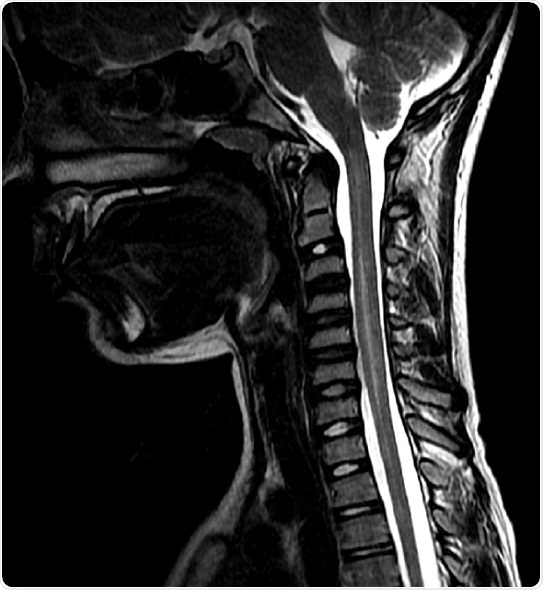

An MRI of a patient with AFM. The lightening on the spinal cord is due to inflammation. Credit: Johns Hopkins Medicine

AFM is a rare condition that causes inflammation and damage to the spinal cord in children, resulting in a sudden paralysis of arms and/or legs and loss of muscle strength and reflexes. Other symptoms can include facial drooping, difficulty swallowing, slurred speech and trouble breathing.